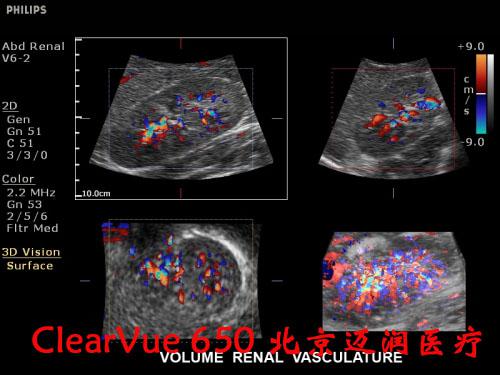

飛利浦ClearVue?CV650彩超

飛利浦ClearVue CV650(HD11XE升級版)是集成了飛利浦多項先進超聲技術(shù)的全身應(yīng)用型實時三維彩色超聲診斷系統(tǒng),采用了飛利浦最新的“元設(shè)計”理念。在原始信號的采集上,CV650飛利浦專利的超聲探頭微信號處理技術(shù)(雙A探頭技術(shù)),保證了零損耗寫真級實時數(shù)據(jù)采集,呈現(xiàn)更真實的圖像信息,可以大大減少臨床上的誤診與漏診的發(fā)生率。

良好的二維成像技術(shù)是保證實時三維圖像質(zhì)量的關(guān)鍵。CV650的實時三維成像融合了飛利浦傳統(tǒng)的優(yōu)勢技術(shù)SONOCT和Xres,保證了良好的圖像分辨力和對比度;另外,容積探頭也采用了“雙A探頭技術(shù)”,能夠?qū)崿F(xiàn)原始信號的零損耗,使呈現(xiàn)的三維圖像效果更逼真。同時,高速的處理內(nèi)核能使容積探頭實現(xiàn)最大48幁/秒的掃描速率,完成一次靜態(tài)掃描的時間也只需要2秒鐘,這些都保證了容積成像的可操作性。

該設(shè)備凝聚了前沿的圖像處理技術(shù)和實用的臨床解決方案,ClearVue CV650適用于腹部、婦產(chǎn)科、小器官、兒科、心臟、外周血管、泌尿系、肌肉骨骼以及術(shù)中檢查和介入診斷治療。

飛利浦ClearVue 650超聲系統(tǒng)臨床高清圖片